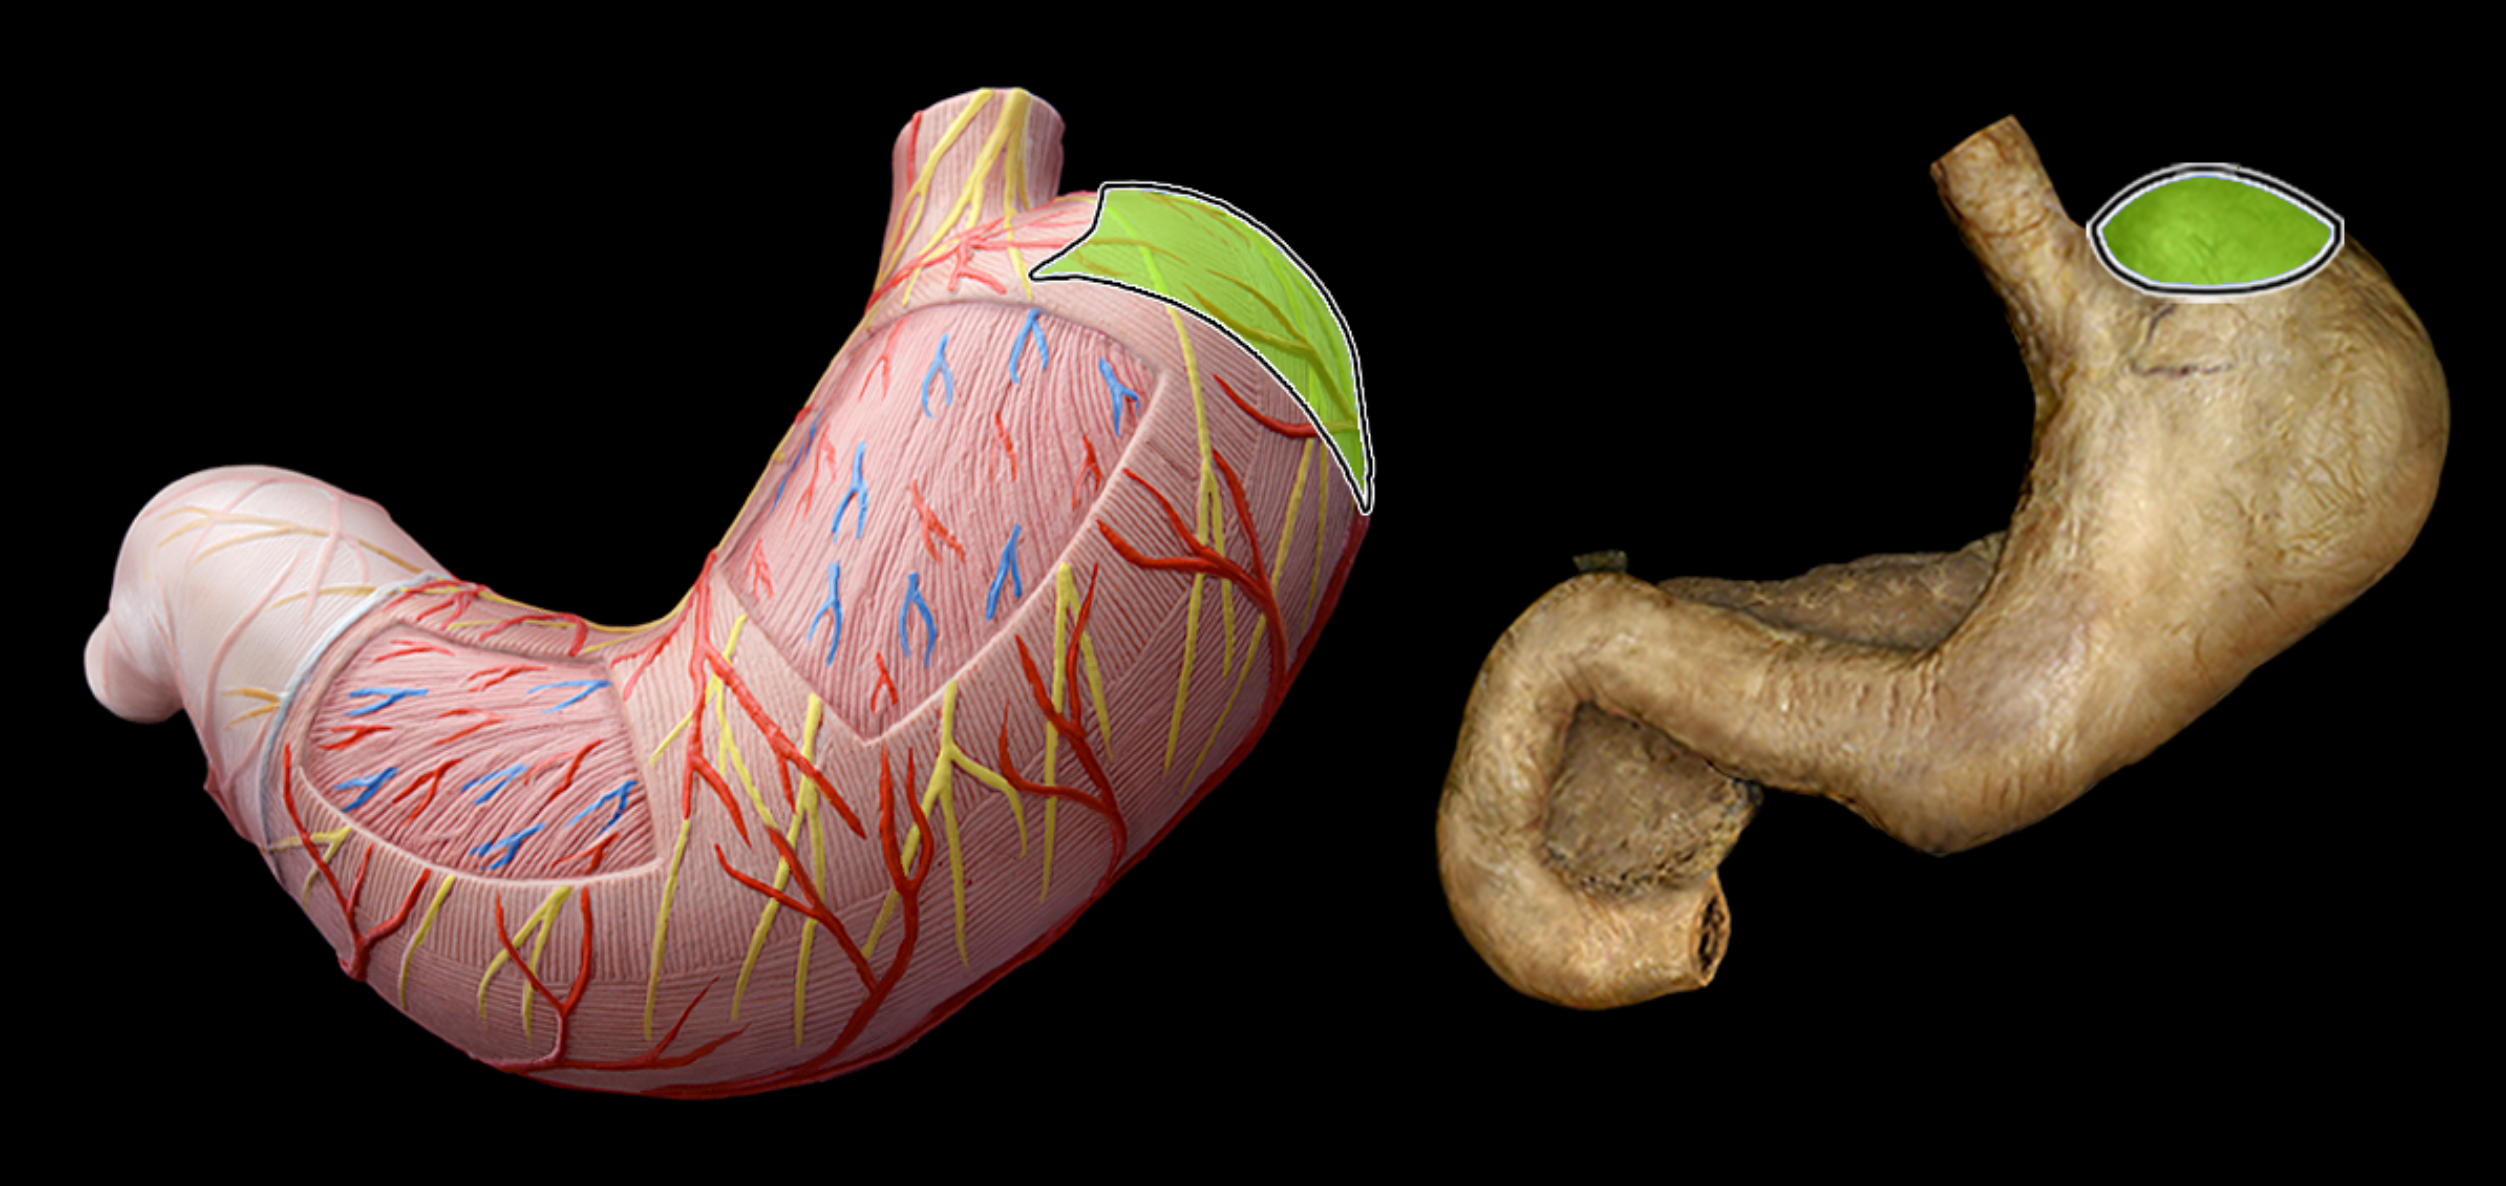

Pyloric part of stomach

Fundus of stomach

cardia of stomach